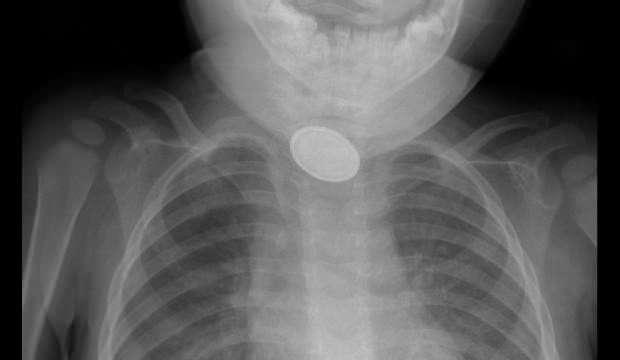

Kayseri’de 15 aylık bebeğin yemek borusuna pil ve lego parçası kaçtı

Yaklaşık 3 saatlik süren operasyonun ardından A.Y.Ç.'nin yemek borusuna kaçan düğme pil ile lego oyuncak parçası çıkarıldı.